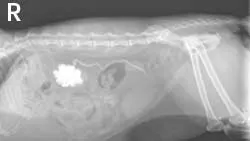

ImagingAbdominal radiographs showed small irregular kidneys (Figure 1, right: Radiograph of the right lateral abdomen. The kidneys are small and irregularly shaped. Mineral densities are visible in the left kidney. View larger image), and irregular margins were evident in ultrasound imaging (Figure 2, below: Ultrasound of the left kidney demonstrating irregular margins. View larger image).

Static left renal disease and mild hydronephrosis of the right kidney with proximal hydroureter were evident on renal ultrasonography (Figure 3, right: Ultrasound of the right kidney showing pelvic dilation. View larger image). Renal calculi were present bilaterally.